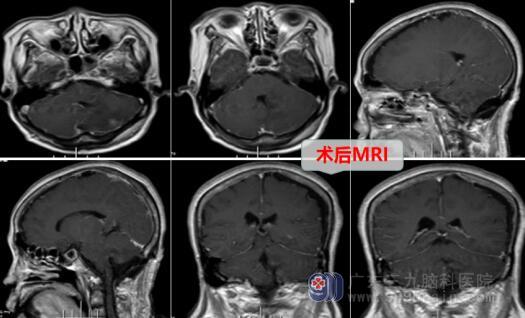

医疗团队经过详细的病情讨论及手术预案后进行了“左侧小脑半球、蚓部-四脑室肿瘤切除术”,术中肿瘤质韧边界清晰,位于左侧小脑半球至小脑蚓部达四脑室,术中病理考虑脑膜瘤待排神经鞘瘤,结合术前患者无明显神经功能损伤,倾向脑膜瘤诊断;术中顺利全切肿瘤,出血少量,损伤轻微。

术后林阿姨很快恢复意识,肢体活动良好,顺利进入康复期。